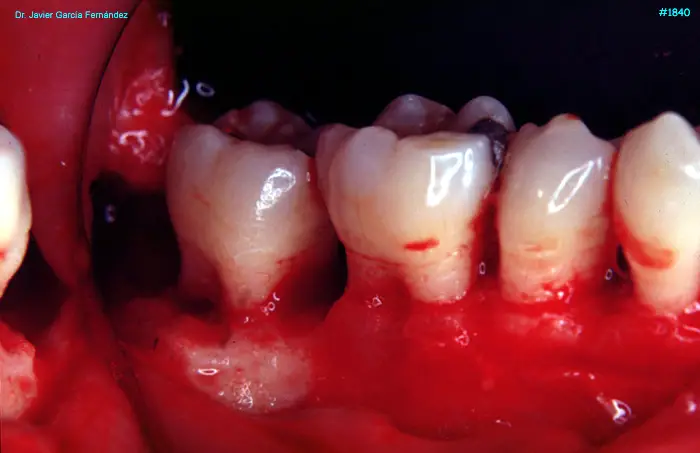

image 106